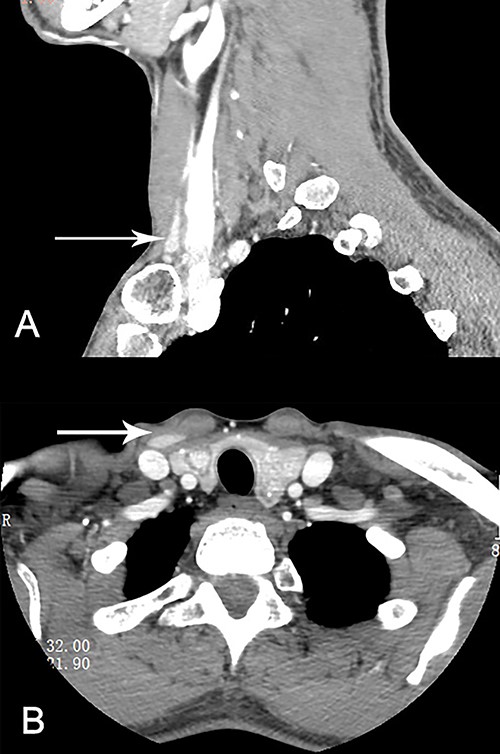

The patient was hospitalized in 22 March 2021. The level of thyroglobulin was as high as 230.80 ng/ml, whereas all other thyroid functional indicators were normal. Chest and abdominal examination as well as preoperative fiberoptic laryngoscopy were all normal. He underwent contrast-enhanced cervical computed tomography (CT) scan, which confirmed bilateral possible malignant nodularity in thyroid gland and an ~1.6 × 0.6-cm hyperdensity deep to the right sternocleidomastoid muscle (SCM, Fig. 1A). Total thyroidectomy and bilateral central neck dissection was operated. A metastatic lymph node encapsulated the left recurrent laryngeal nerve. In the same time, the mass lateral to the right SCM was removed, which was separated from the thyroid gland (Fig. 1B). Intraoperative neuromonitoring information was normal. Pathology demonstrated bilateral papillary thyroid cancer (the size of cancer in left lobe was 2.2 cm, right 1.6 cm) with three lymph node metastases. However, the aberrant thyroid was histological free of cancer. Postoperative radioactive iodine therapy (RAI) was recommended for this patient.

Ectopic lateral thyroid in CT (as is shown in white arrow in A and B).